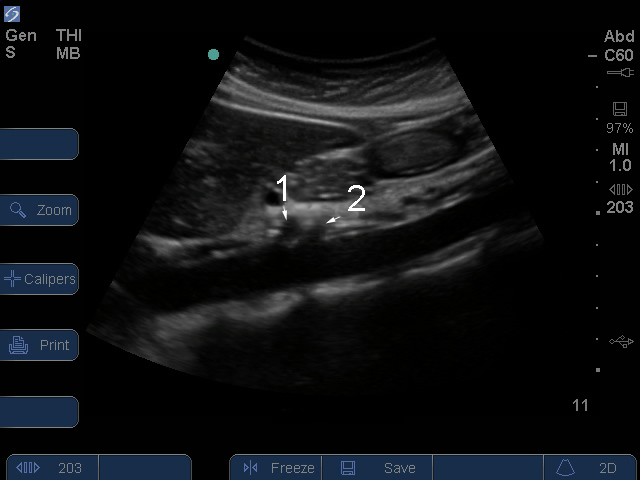

Bild: S Series, proximale Aorta/Truncus coeliacus - Arteria mesenterica superior (AMS), Arterien

Aorta abdominalis

1. Truncus coeliacus

2. Arteria mesenterica superior (AMS)